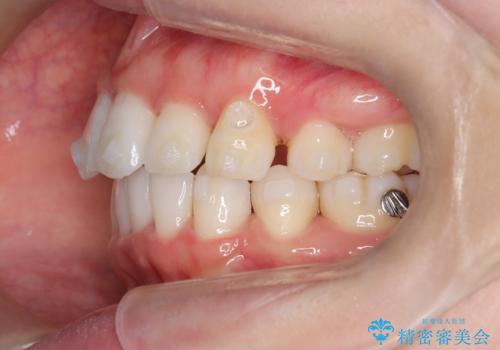

【抜歯インビザ】凸凹を綺麗になおしたい

- 前歯の凸凹を主訴に来院されました。

叢生量が多いため、抜歯が必要となるため、ワイヤー矯正をお勧めしましたが、患者さんの希望によりインビザラインで治療を開始しました。途中でワイヤーリカバリーを必要とせず終了でき患者さんには満足していただけました。

ワイヤー矯正よりも期間がかかっています。